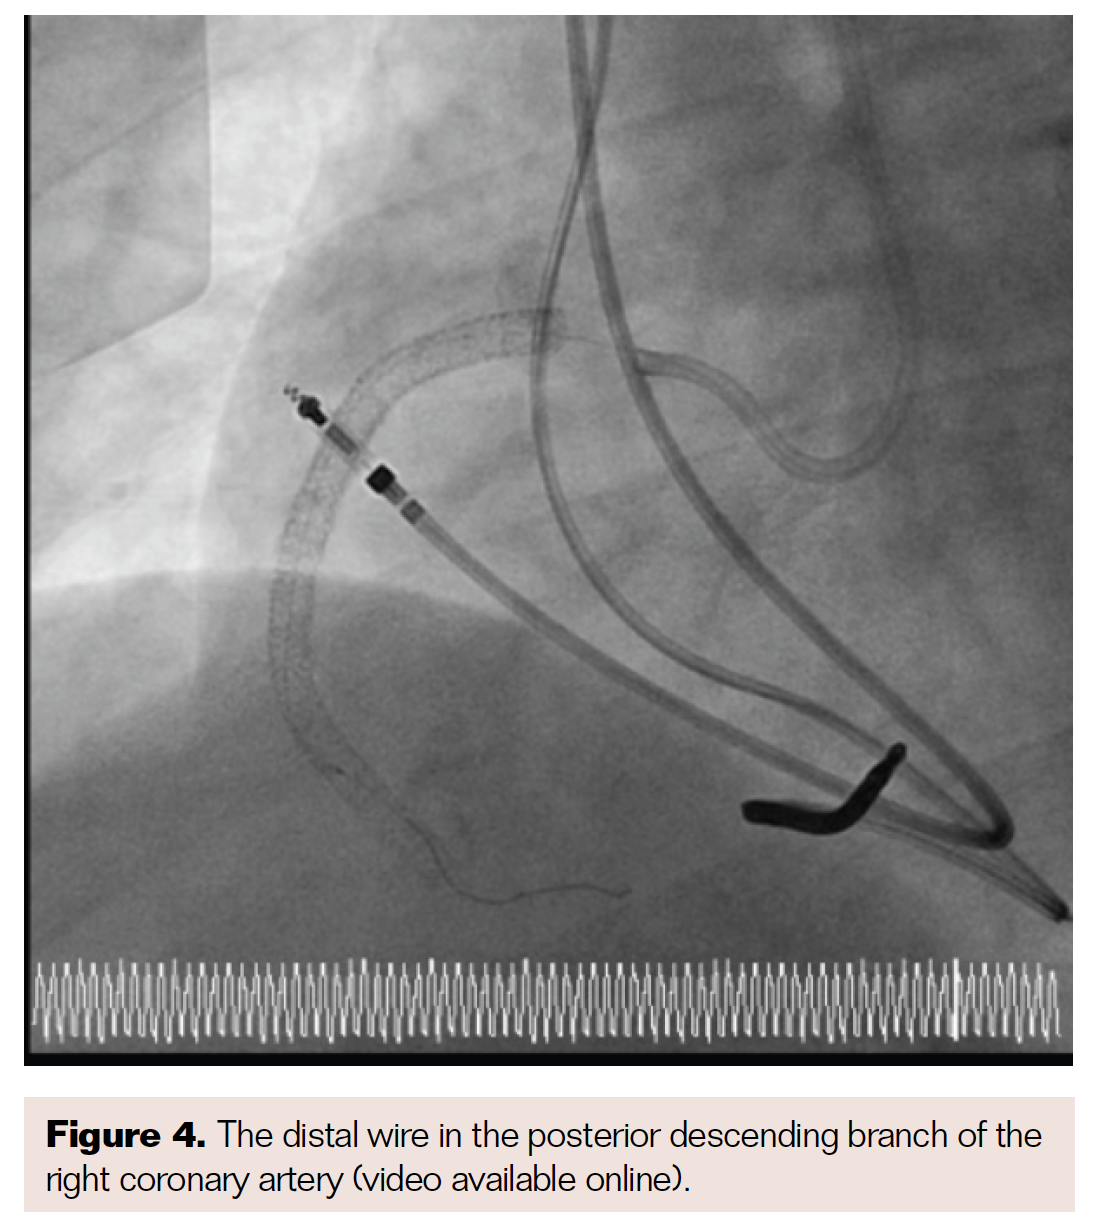

Due to continued increasing angina, the patient was evaluated by our group, and we attempted to recanalize the RCA with standard techniques via the radial approach (Figure 1). After these techniques failed, the patient returned for another session. We used the step-by-step method in an attempt to recanalize the RCA using the CrossLock device (Radius Medical) and Indigo CAT RX aspiration catheter (Penumbra) to remove any thrombus. The step-by-step technique for occluded vessels is typically performed only in the peripheral vessels. We have used the step-by-step technique in the coronary arteries for in-stent restenosis, though only with a centering device such as the CrossLock device.

We entered from the right groin, and, using an 8 French right coronary artery Judkins guide catheter (Medtronic), passed the CrossLock device, as well as an 0.9 mm excimer coronary laser angioplasty (ECLA) catheter (Philips), and a Miracle 3 wire (Asahi Intecc). After entering the proximal third of the chronic total occlusion (CTO), we switched to a 7 French Amplatz guide catheter (Boston Scientific) and a Fielder XT guidewire (Asahi Intecc) (Figure 2). With the Fielder, we were able to travel approximately halfway across the vessel and address the lesion with the laser. We then passed the Whisper wire (Boston Scientific) into the posterior branch of the RCA, completely recanalizing the CTO (Figure 3). After recanalization, we performed balloon angioplasty with a 1.5 mm Somerset balloon (Terumo), followed by a 4 mm balloon in the proximal portion of the in-stent restenosis (Figures 4-5).